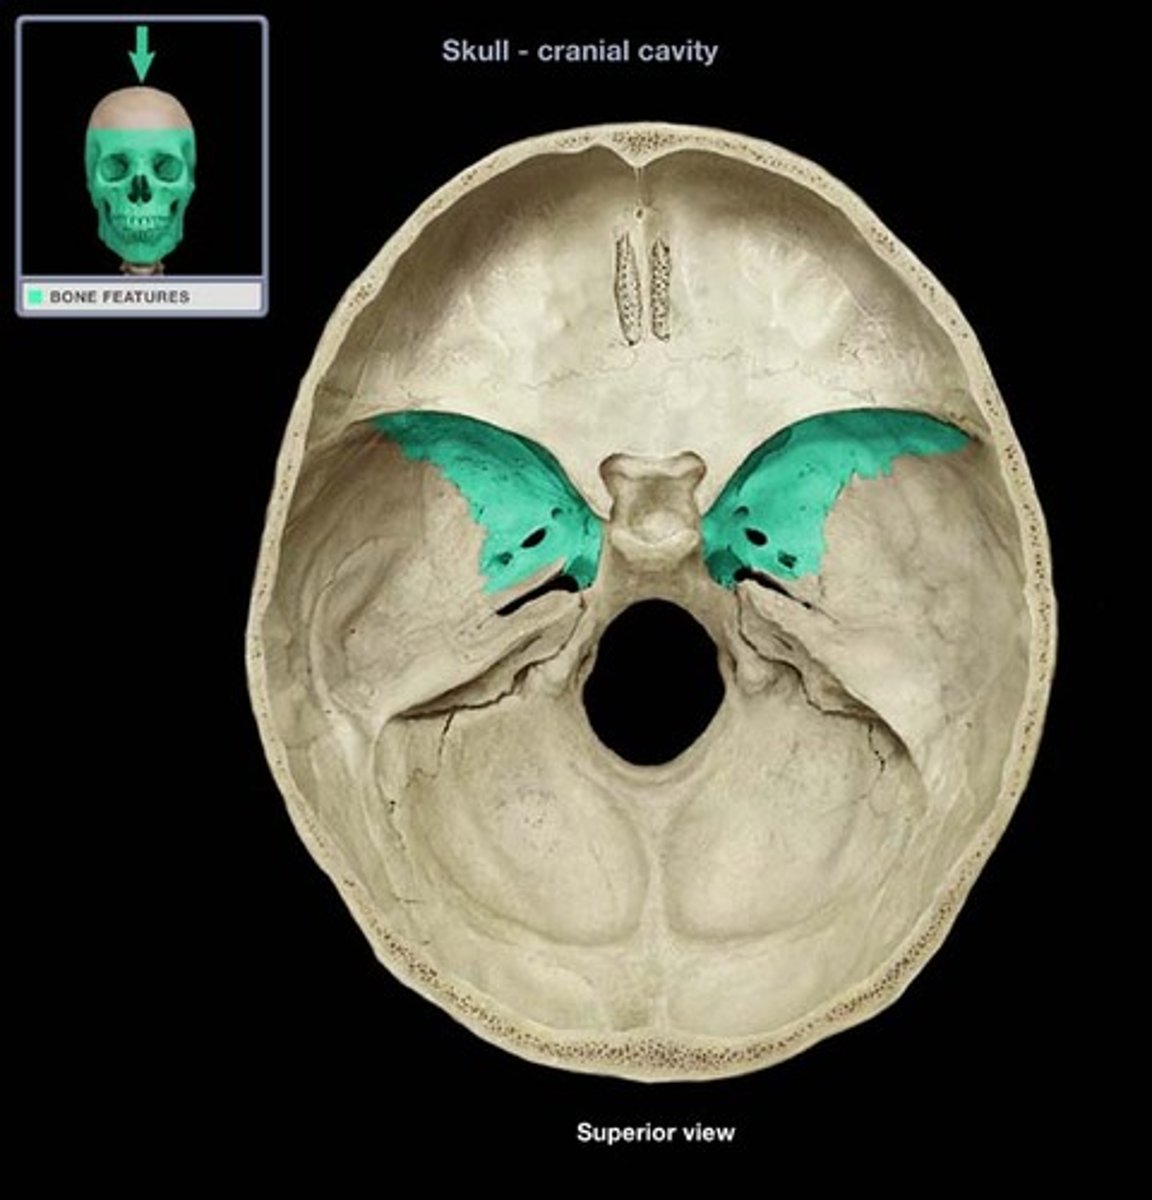

Greater wings

Less wings